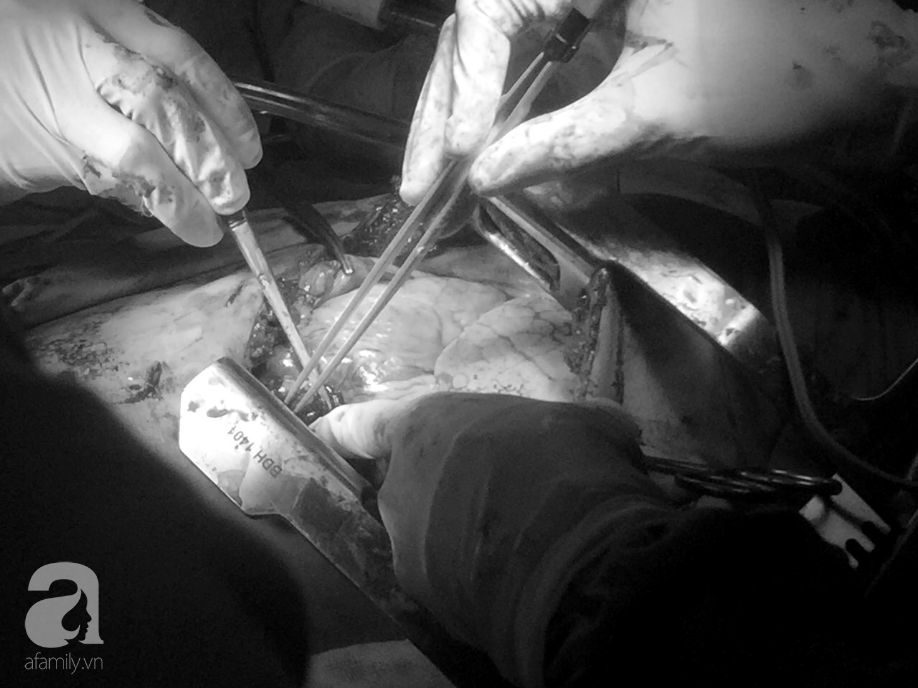

Ca phẫu thuật phối hợp giữa BV Bình Dân và BV CTCH TP.HCM.

20 phút sau, các bác sĩ ở BV Bình Dân đã có mặt. Ekip phẫu thuật của hai BV đã phối hợp khâu lại vết rách ở thành tâm thất trái, khâu vết rách ở thùy trên phổi phải, vết rách cơ hoành, dẫn lưu kín khoang màng phổi…Sau 105 phút, ca phẫu thuật hoàn thành.